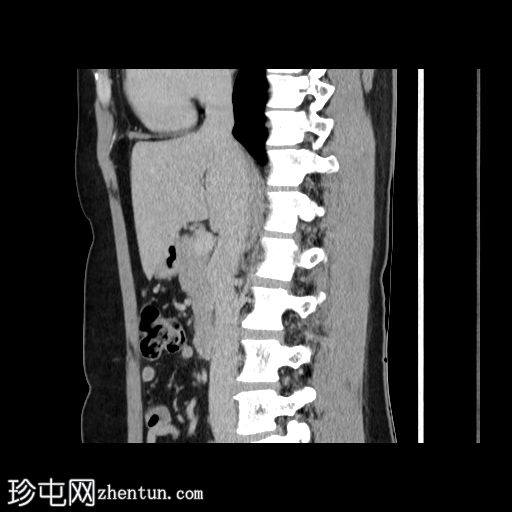

冠状面C+期

动脉期

在轴向、冠状面和矢状面上均可见肝5/6段病变。动脉期可见周围结节状强化,门静脉期可见进行性向心性充盈,延迟期亦持续存在。这些表现为肝血管瘤的特征性表现。